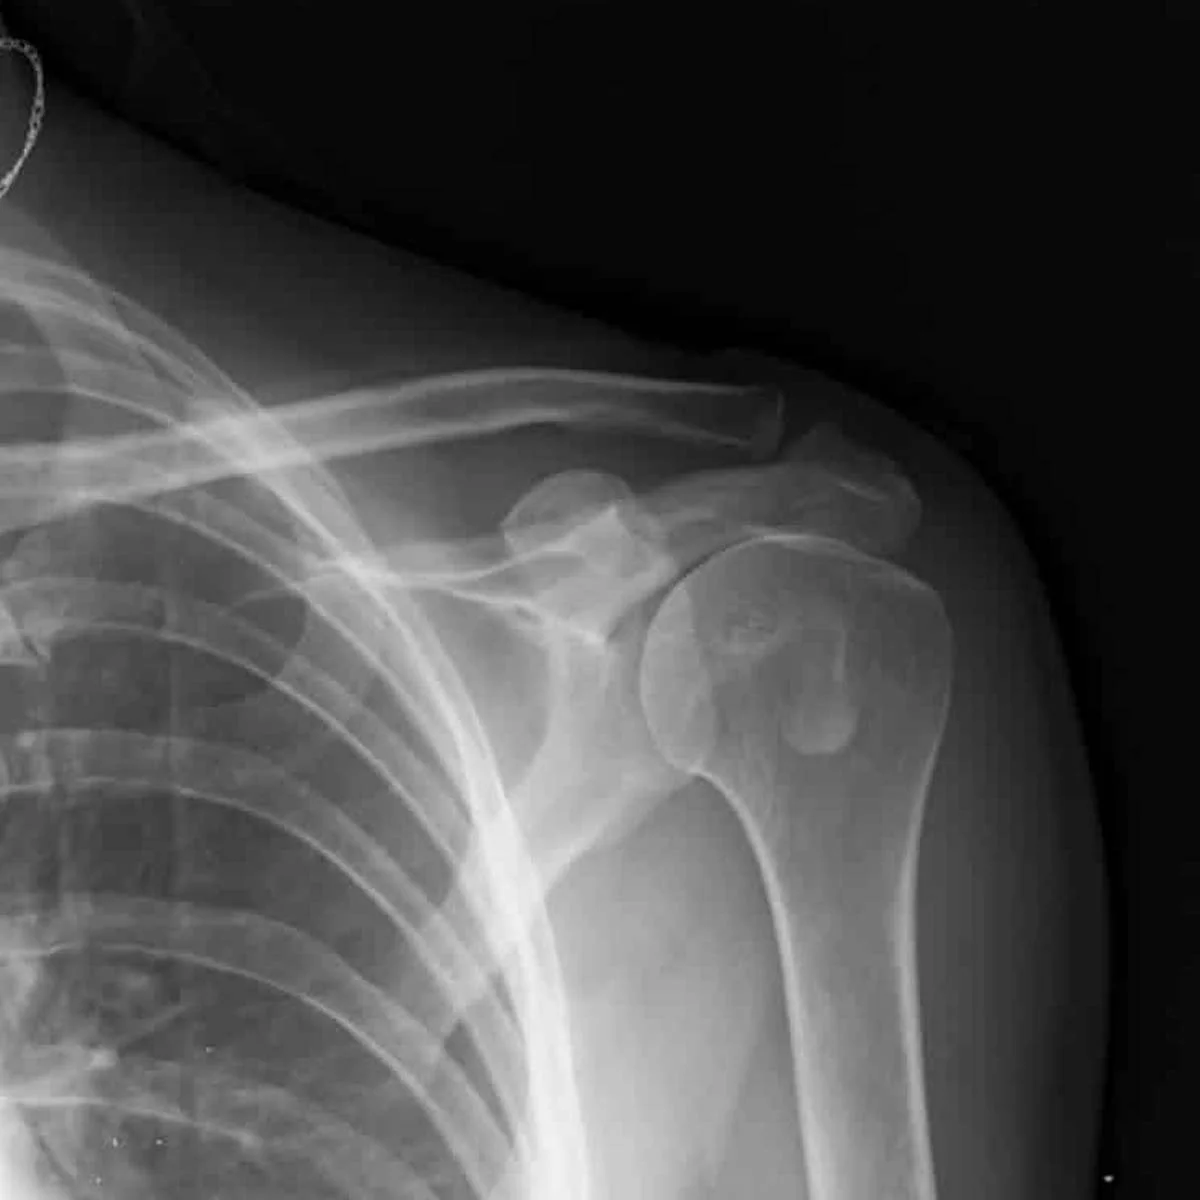

Luxación aguda y recurrente de hombro

Es una lesión traumática en la que la cabeza del húmero se desplaza fuera de la cavidad glenoidea, generalmente debido a caídas, golpes o movimientos bruscos.